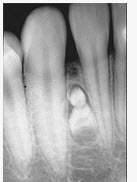

组图为牙瘤的外观及X线表现,有关此病的描述错误的是()

A、多见青年人

B、生长缓慢,早期无自觉症状

C、由牙胚组织异常发育增生而形成

D、X线可见类似发育不全牙的影像

E、绝大多数为恶性

E